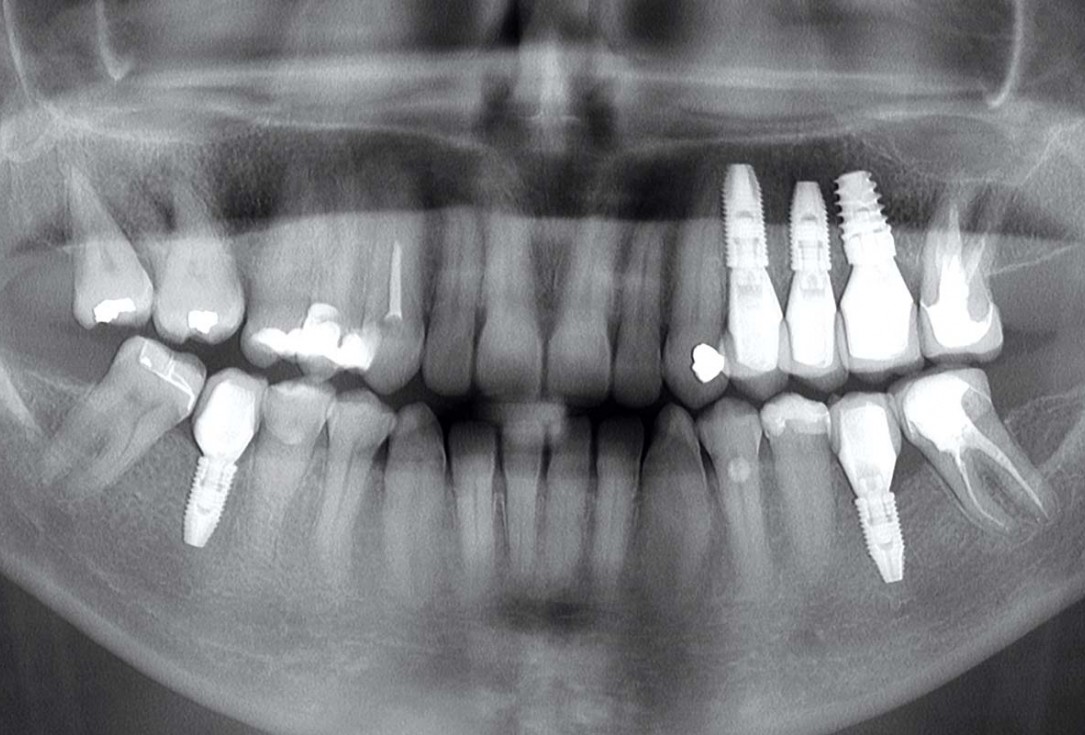

1/13 - Pre-operative OPG, teeth 24, 25, and 26 planned for extraction

Multiple socket preservation in the maxilla with collacone® max – Dr. D. Jelušić